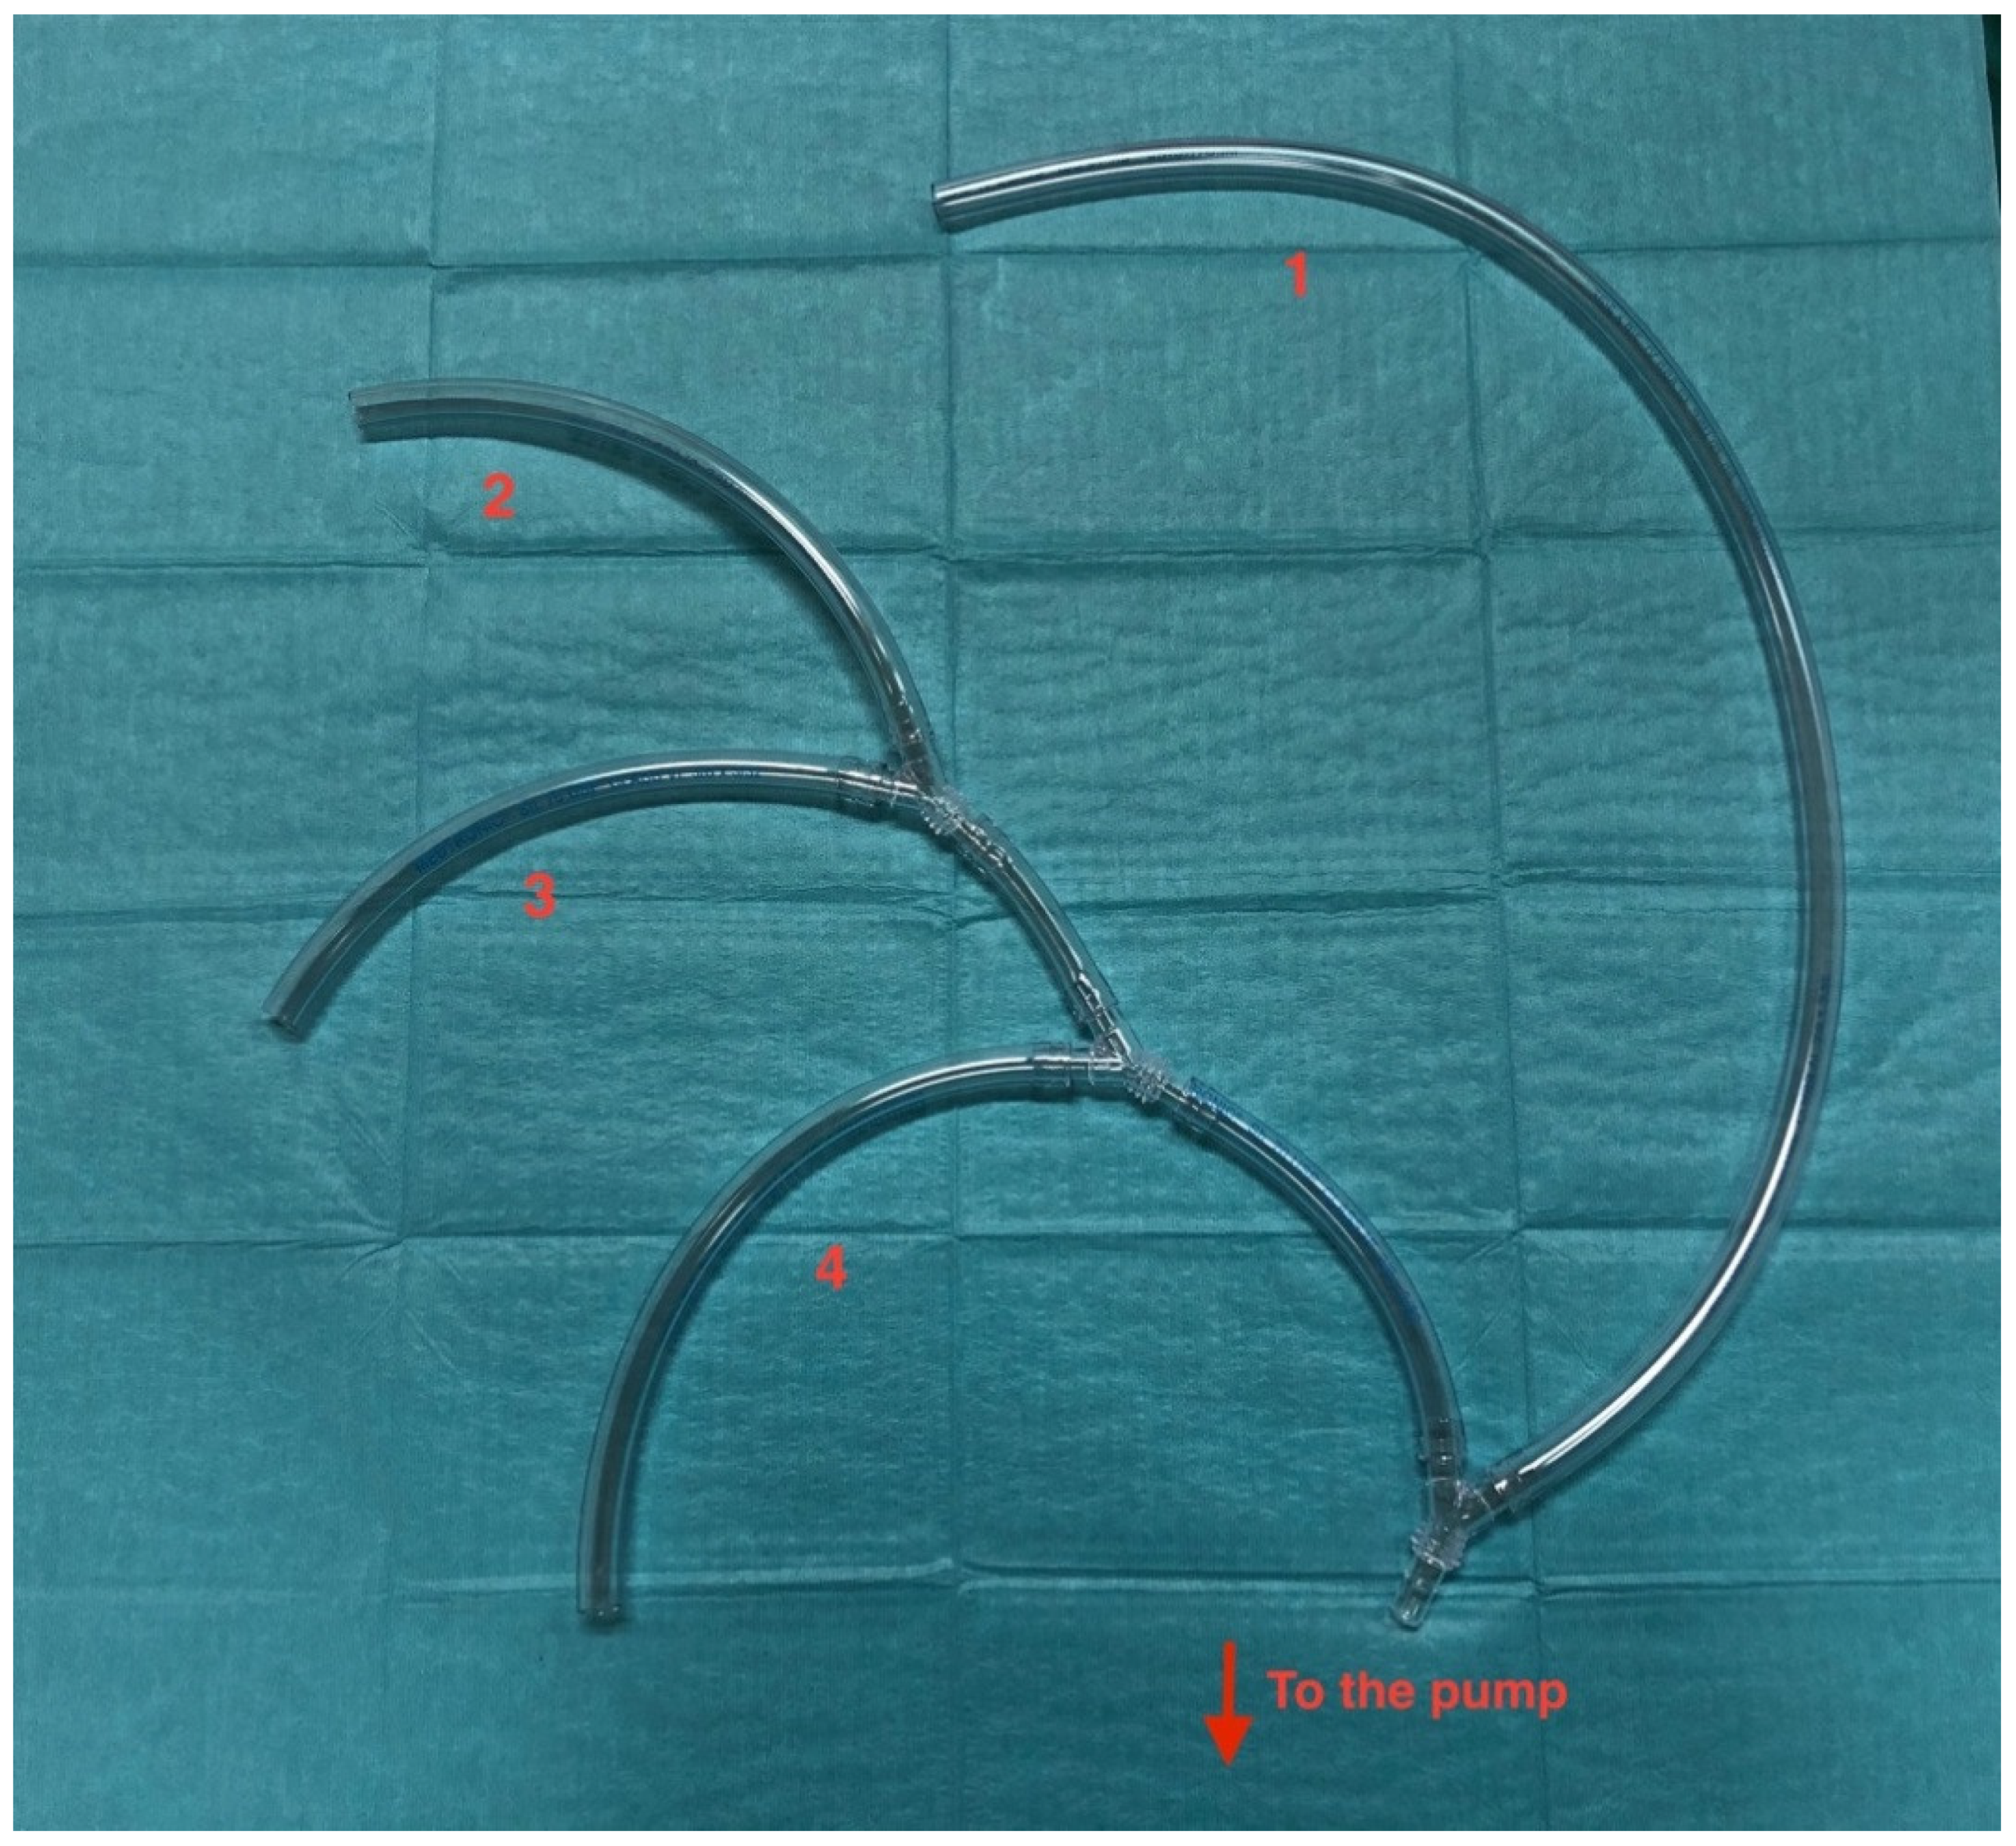

- Masiello, P.; Mastrogiovanni, G.; Chivasso, P.; Triggiani, D.; Cafarelli, F.; Iesu, S. A modified frozen elephant trunk hybrid device to facilitate supra-aortic trunk anastomosis. J. Card. Surg. 2021, 36, 371–373. [Google Scholar] [CrossRef] [PubMed]